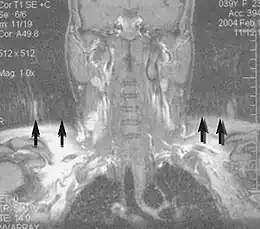

Neuroimaging

MRI is the investigative tool of choice for neurological cancers over CT, as it offers better visualization of the posterior cranial fossa, containing the brainstem and the cerebellum. The contrast provided between grey and white matter makes MRI the best choice for many conditions of the central nervous system, including demyelinating diseases, dementia, cerebrovascular disease, infectious diseases, Alzheimer's disease and epilepsy.[31][32][33] Since many images are taken milliseconds apart, it shows how the brain responds to different stimuli, enabling researchers to study both the functional and structural brain abnormalities in psychological disorders.[34] MRI also is used in guided stereotactic surgery and radiosurgery for treatment of intracranial tumors, arteriovenous malformations, and other surgically treatable conditions using a device known as the N-localizer.[35][36][37] New tools that implement artificial intelligence in healthcare have demonstrated higher image quality and morphometric analysis in neuroimaging with the application of a denoising system.[38]